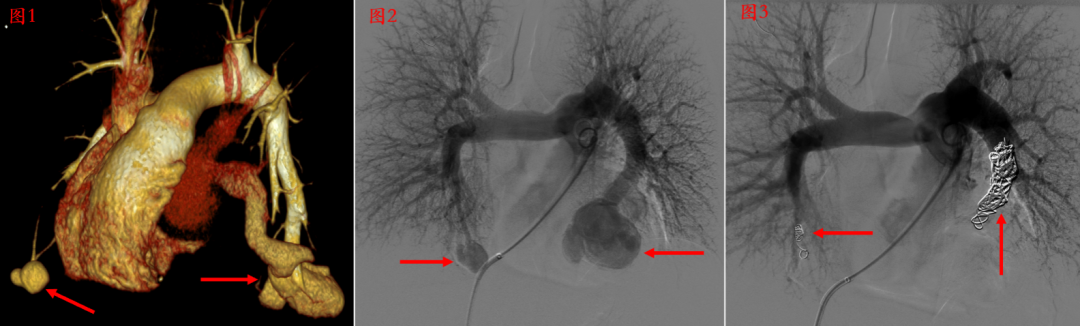

Case 1,弹簧圈栓塞肺动静脉瘘

图1,肺动脉CTA显示双侧肺动静脉瘘(箭头所指);图2 ,行肺动脉造影显示双侧肺动静脉瘘(箭头);图3,用弹簧圈栓塞后双侧肺动静脉瘘即刻消失。(箭头所指为弹簧圈)